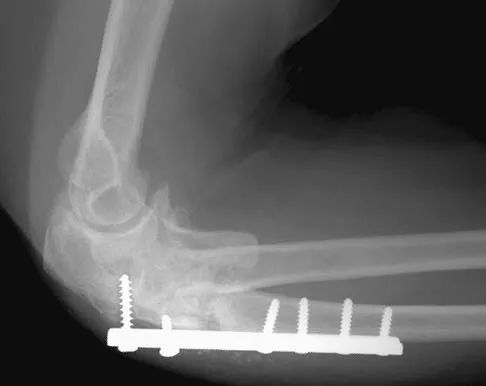

A 54-year-old woman sustained an elbow injury 3 months ago that was treated with open reduction and internal fixation. She now reports pain and limited elbow motion. Radiographs are shown in Figures 10a and 10b. Treatment should now consist of

Explanation

Radiographs reveal malunion of a Monteggia fracture-dislocation. Dislocation of the posterior radial head is caused by the malunited ulnar fracture. The deformity includes shortening with an apex posterior angulation. In the acute setting, open reduction of the radial head rarely is necessary; however, in chronic dislocations, open reduction is required. Without ulnar osteotomy, recurrent radial head dislocation is likely.